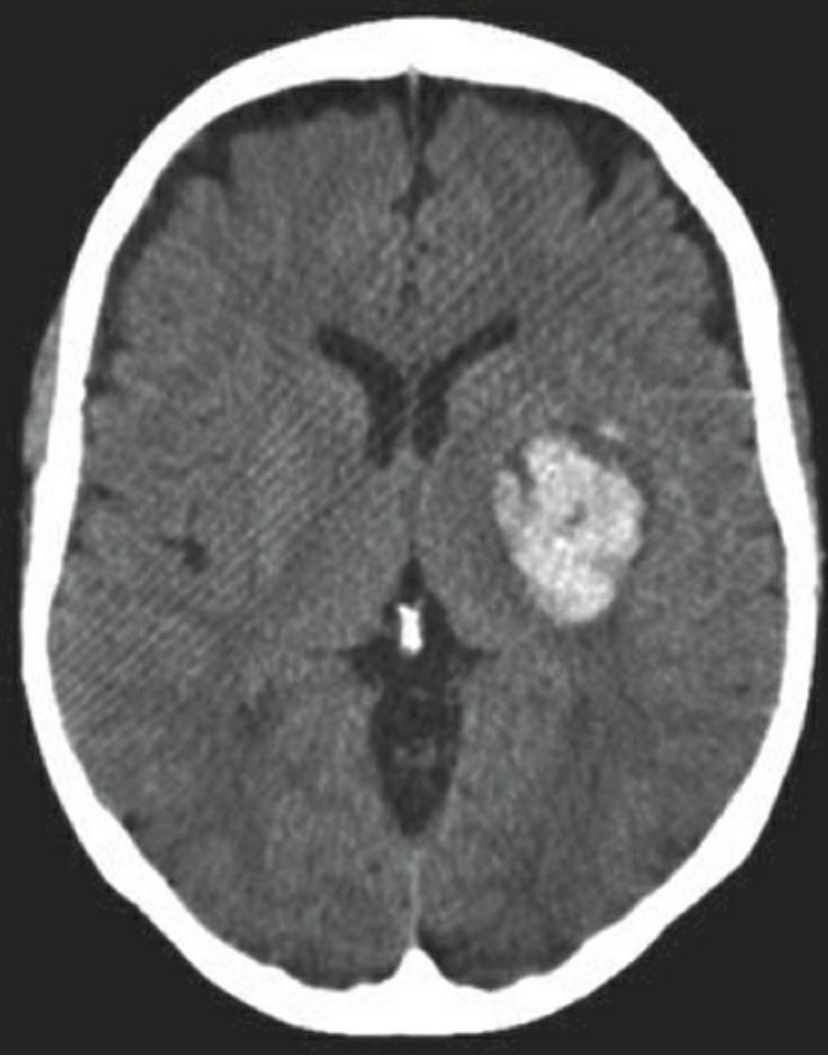

Xuất huyết trong não(ICH)

Đột quỵ xuất huyết não (Hemorrhagic Stroke)